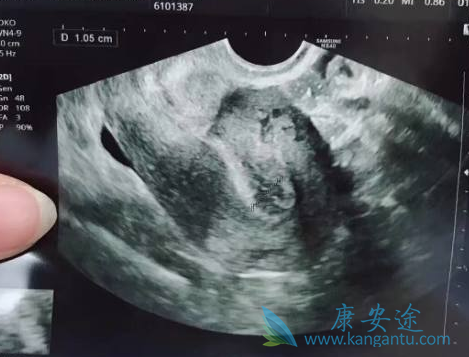

进行体外受精:试管婴儿医生将男方取出的精液采用上游法或Percoll密度梯度离心法处理。在取卵后4至5小时后,便将精子与卵子放在同一个培养皿中,进行培养胚胎,当培养到18小时后,显微镜下观察受精如果顺利,便会有一些受精的胚胎。胚胎移植:医生在选择优秀的胚胎以后,会将两三个胚胎移植到女方的子宫。为了更好地保护胎儿,一般女方还需要注射黄体酮,以助于胚胎着床,促进胎儿生长。妊娠的确定:在胚胎移植后的第14天,还要进行验晨尿或抽血检查,以确定是否妊娠。在胚胎移植后的一个月时,要进行一次B超检查,查看胎儿数以及胚胎着床部位和胎儿心跳。这个时候试管婴儿的整个流程也就结束了,